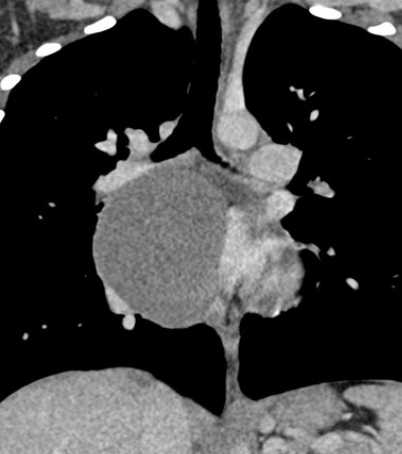

- Bronchique = Sous-carinaire++

- Bronchique = paroi fine

- Les deux peuvent avoir un contenu liquidien ou protéique